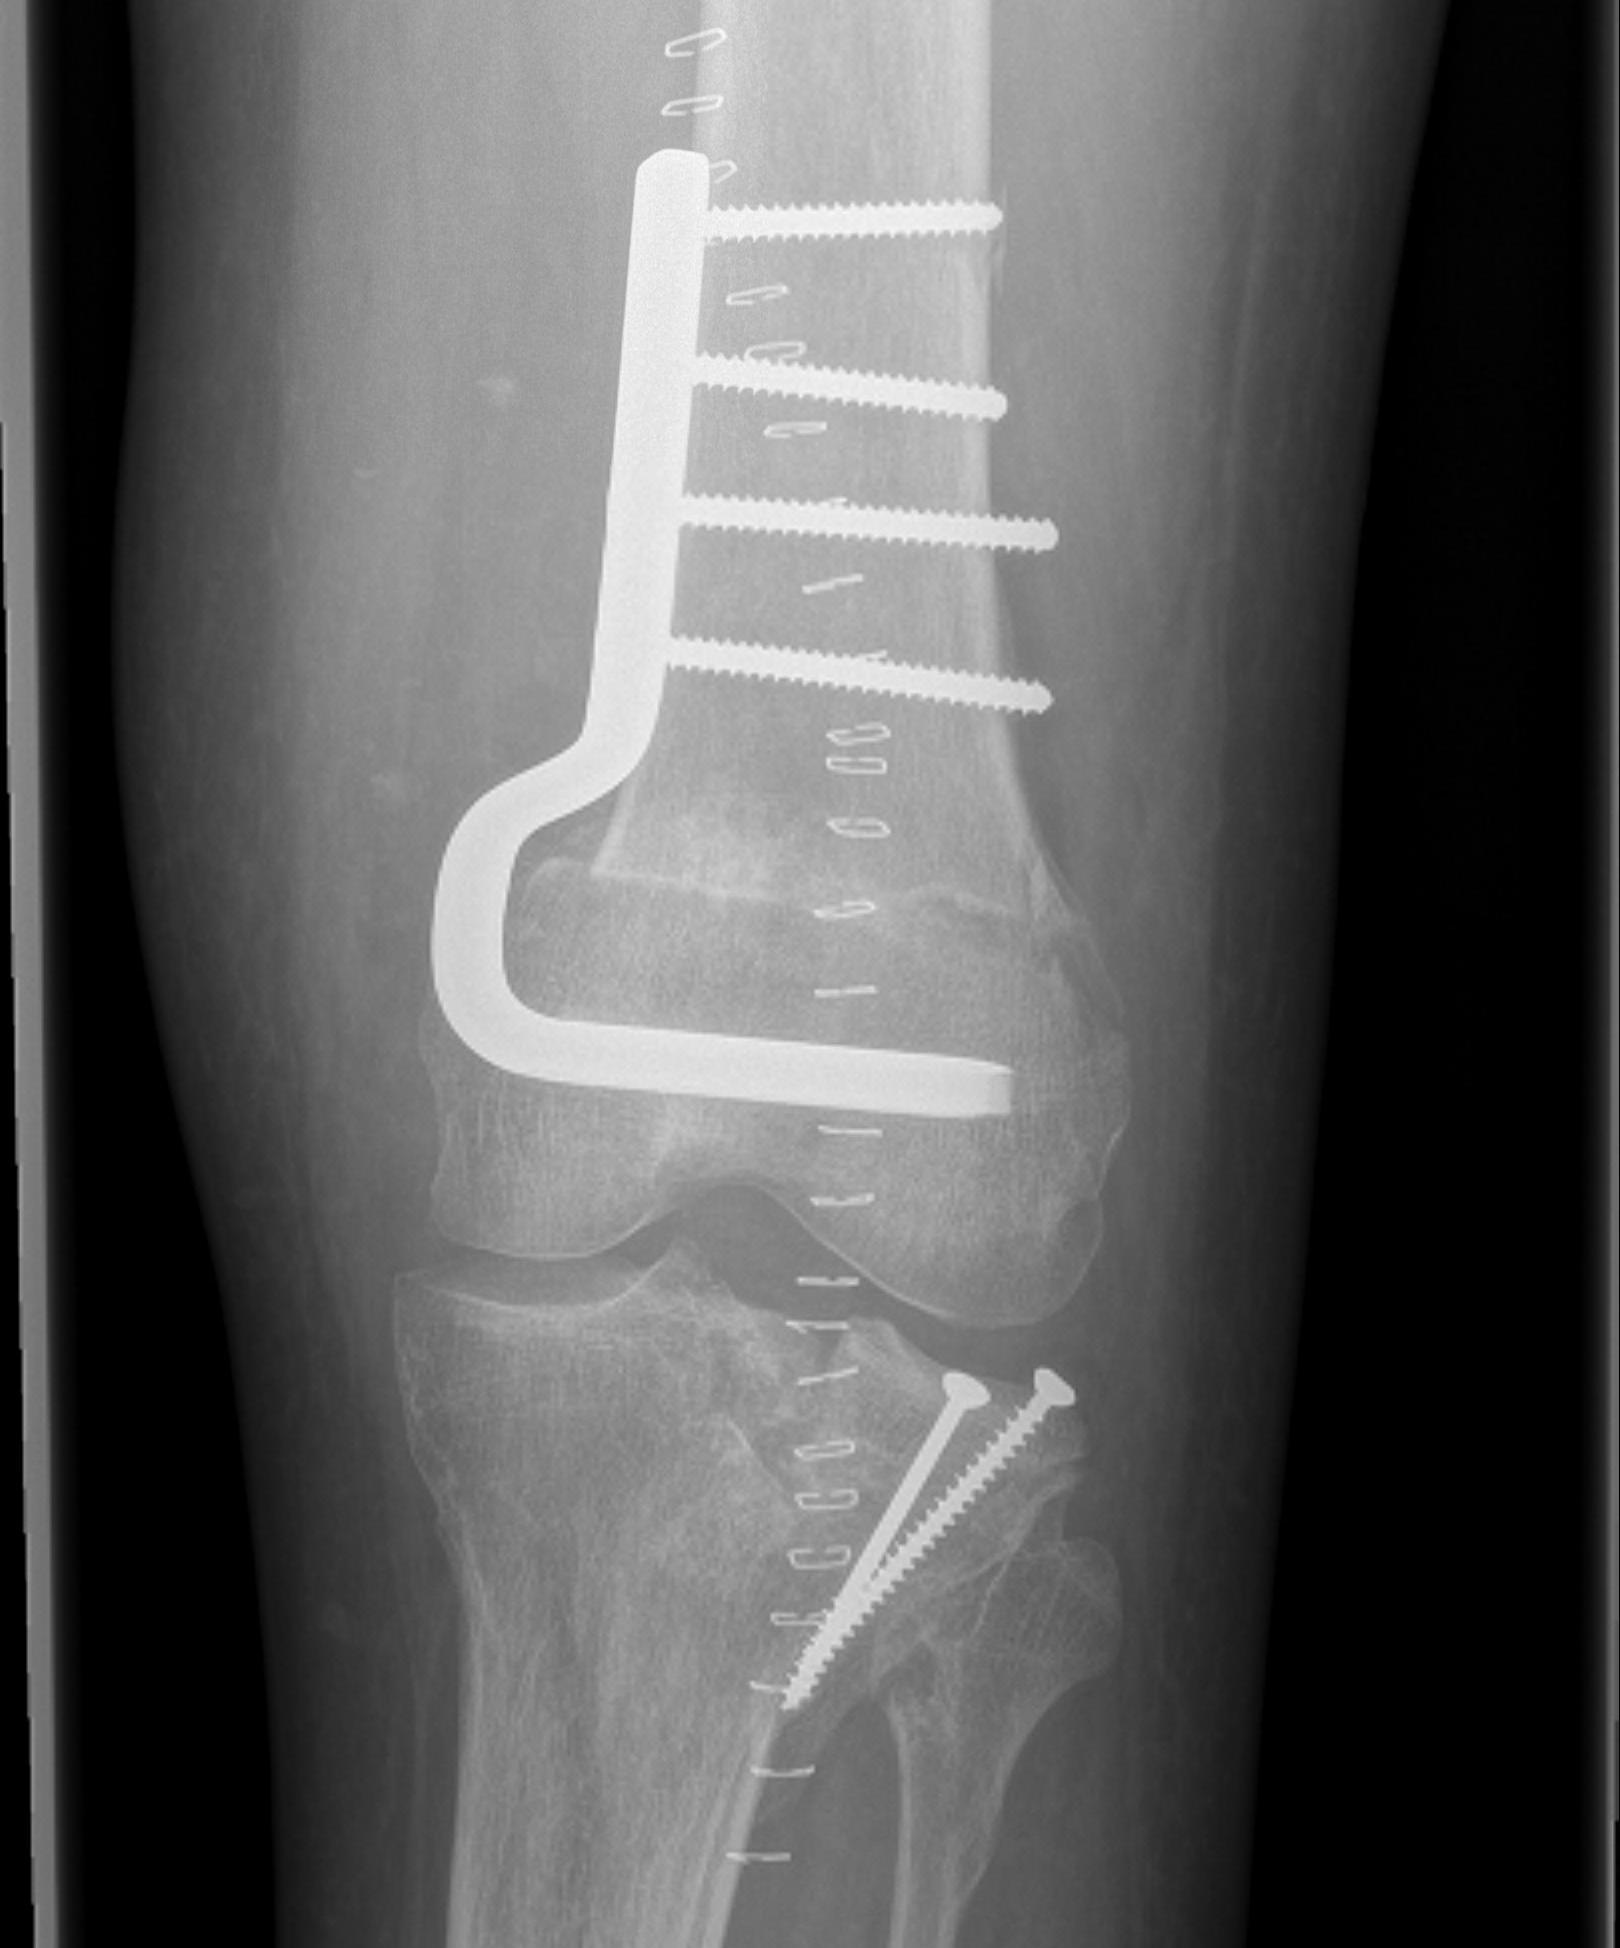

• Cartilage defects

• Background

• Management